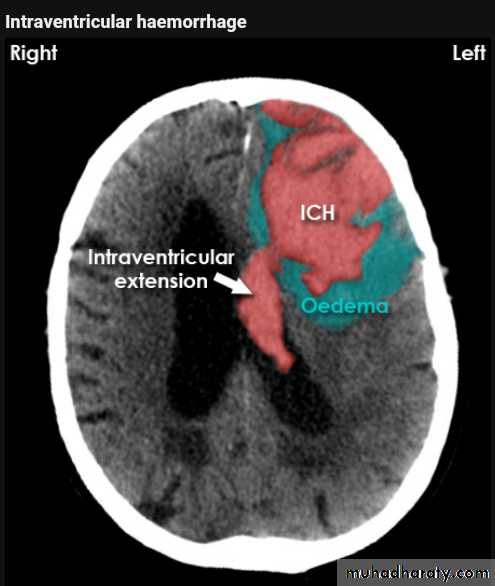

Intra ventricular IVH

Acute Intra cerebral hematoma

CT finding :Hyper dense area , surrounded by edema , any where within the brain parenchyma.

Shifting of the midline

Compression of the ipsi lateral ventricle .